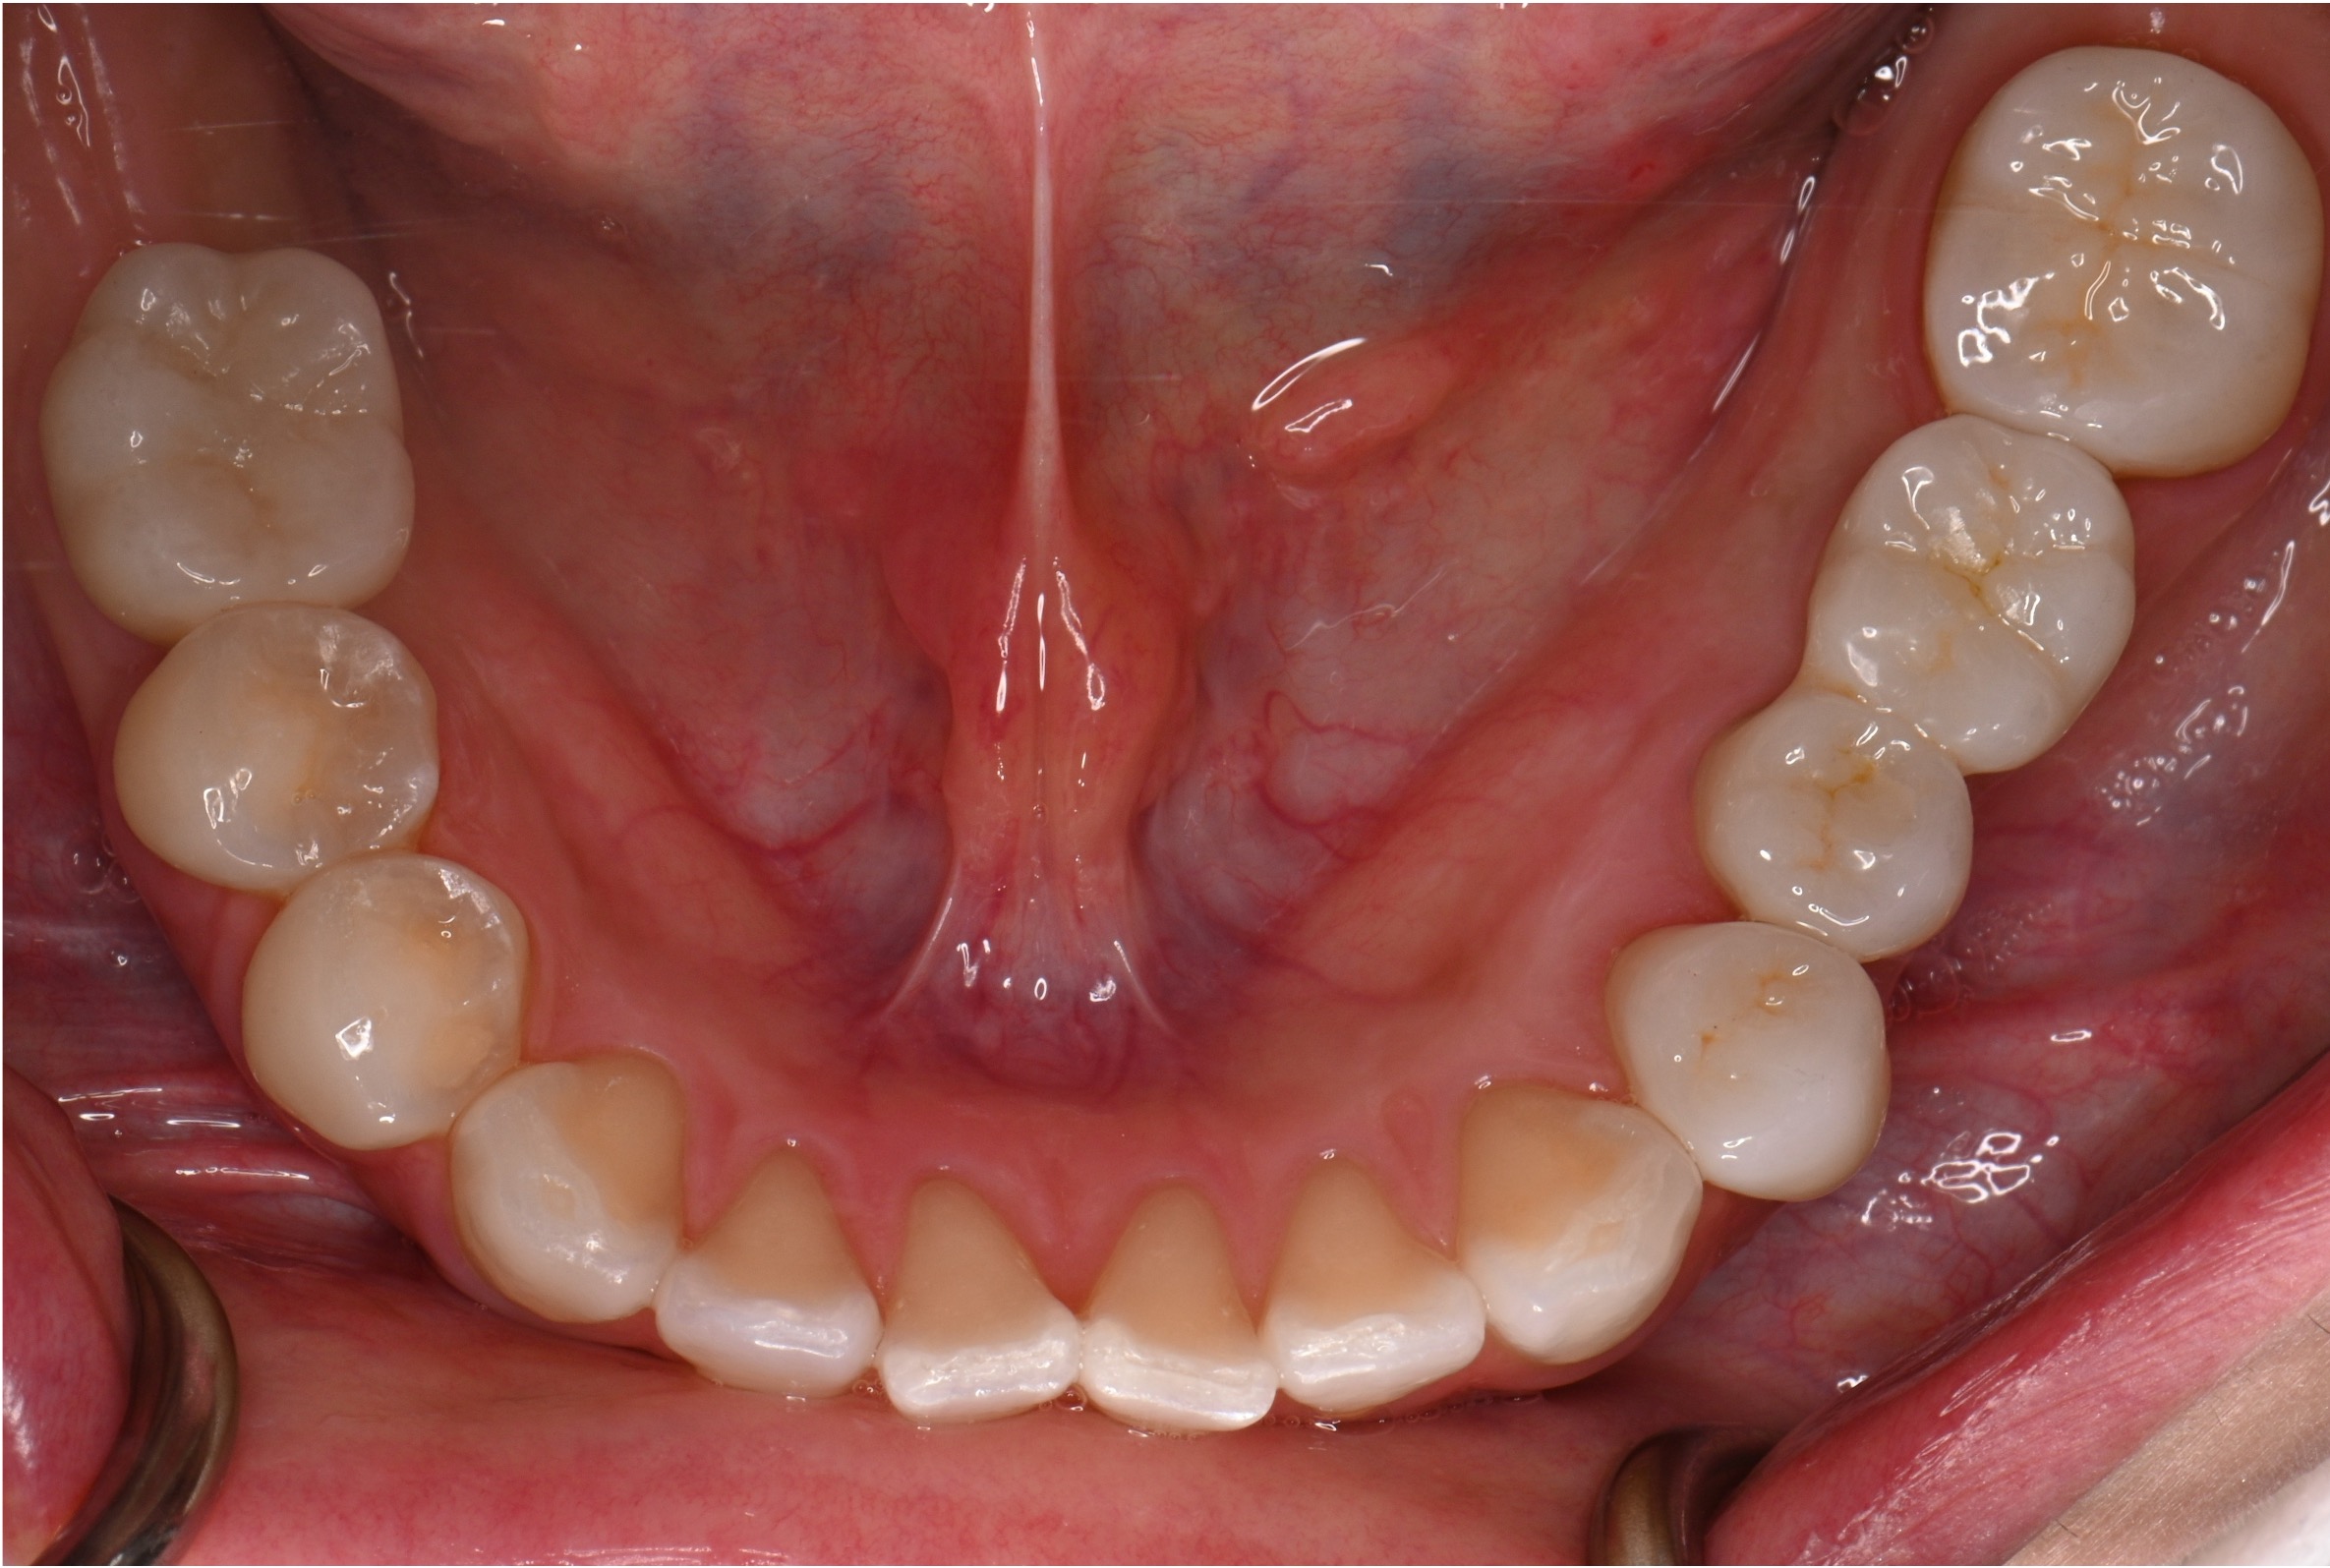

治療前

治療後